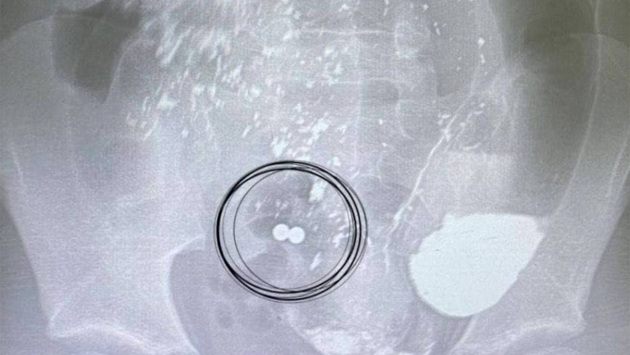

Ребенок несколько дней назад во время игры съел два металлических магнита. Испугавшись, он решил ничего не будет говорить родственникам, однако магниты попали в разные отделы кишечника, после чего притянулись друг к другу и слепили стенки внутренних органов.

Врачам удалось вовремя оказать помощь мальчику — они извлекли инородные тела и ушили перфоративные отверстия там, где соприкасались тонкая и слепая кишка. Сейчас жизни и здоровью ребенка ничего не угрожает, он идет на поправку. Медработники в свою очередь напомнили детям и родителям о том, что такие ситуации крайне опасны для жизни.